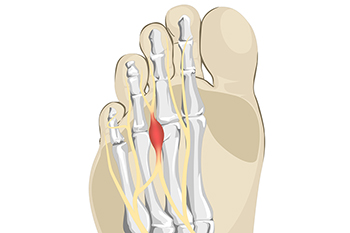

When to Have Foot Surgery

Making the decision about whether to undergo foot surgery is a difficult and highly personalized process. In consultation with a podiatrist and surgeon, you can receive the information you need to make an informed decision. Generally speaking, if you notice that a foot affliction you have is causing your skin to react negatively or your foot to become deformed, foot surgery might be a good option for you. Additionally, if you notice that your affliction is not responding to any medication your podiatrist has prescribed or any orthotics you might be wearing, then foot surgery might be a suitable last resort. There are a variety of conditions that may ultimately merit surgery. For example, particularly bad cases of Morton’s neuroma might require foot surgery. Specifically, the nerve that is affected between the toes because of Morton’s neuroma, may be successfully removed by foot surgery. Of course, foot surgery can also create detrimental consequences in some cases. There may be complications as a result of the surgery or your joint movement may be restricted. Alternatives to surgery might include performing specific exercises or adjusting footwear. You can make this difficult decision about undergoing surgery with the guidance and advice of your podiatrist.

Common Symptoms of Morton’s Neuroma

Research has indicated that the foot condition known as Morton’s neuroma is generally simple to diagnose. The common symptoms that many people experience with this ailment can include a tingling sensation between the second and third toes, or the fourth and fifth toes. It may begin after wearing specific types of shoes, or from walking or standing for an extended period of time. Many people can develop this condition from wearing high heels. This can be a result of a lack of adequate space for the toes to move freely in. A clicking feeling and sound may be felt in the ball of the foot, and it can feel uncomfortable. Many people often equate this feeling with the sensation of stepping on a marble, or having an out of place seam from a sock. Additionally, the toes can separate with a large Morton’s neuroma, and medical attention is needed. The toes may become numb, and it can be quite painful to walk. If you have any of these symptoms, it is advised that you place yourself under the care of a podiatrist who can use various conservative methods, or possibly even perform surgery, to treat Morton’s neuroma.

Morton’s Neuroma

Morton's neuroma is a painful foot condition that commonly affects the areas between the second and third or third and fourth toe, although other areas of the foot are also susceptible. Morton’s neuroma is caused by an inflamed nerve in the foot that is being squeezed and aggravated by surrounding bones.

Morton’s neuroma is a very treatable condition. Orthotics and shoe inserts can often be used to alleviate the pain on the forefront of the feet. In more severe cases, corticosteroids can also be prescribed. In order to figure out the best treatment for your neuroma, it’s recommended to seek the care of a podiatrist who can diagnose your condition and provide different treatment options.